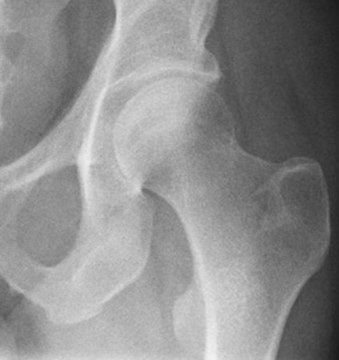

Запитання 19

РОЗПІЗНАЙТЕ КІСТКУ. ПЕРЕЛОМ ЯКОЇ ЇЇ ЧАСТИНИ ВИ БАЧИТЕ НА РЕНТГЕНОГРАМІ?

варіанти відповідей

НЕОПЕРОВАНИЙ ПЕРЕЛОМ ЦІЄЇ КІСТКИ І В ЦЬОМУ МІСЦІ ПРИЗВЕДЕ ДО СМЕРТІ В СЕРЕДНЬОМУ ЧЕРЕЗ КІЛЬКА РОКІВ. А ЦІ РОКИ ПЕРЕТВОРЯТЬСЯ НА СИДЯЧІ АБО ЛЕЖАЧІ МУКИ. ЯКОЇ КІСТКИ І ЯКОЇ ЇЇ ЧАСТИНИ?

HUMERUS, ХІРУРГІЧНА ШИЙКА

ВЕРХНЬОГО ДІАФІЗА

FEMUR, ШИЙКА

ULNA, ШИЙКА

ПРОКСИМАЛЬНОГО ЕПІФІЗА

ДИСТАЛЬНОГО ЕПІФІЗА

HUMERUS, ШИЙКА

RADIUS, ШИЙКА

ПЕРЕЛОМ ЯКОЇ КІСТКИ І В ЯКІЙ ЇЇ ЧАСТИНІ ВИ БАЧИТЕ?

ГОЛОВКИ HUMERUS

ДИСТАЛЬНОГО ЕПІФІЗА HUMERUS

ШИЙКИ FEMUR

ГОЛОВКИ FEMUR

ГОЛОВКИ RADIUS

ПРОКСИМАЛЬНОГО ЕПІФІЗА HUMERUS

ХІРУРГІЧНОЇ ШИЙКИ HUMERUS

АНАТОМІЧНОЇ ШИЙКИ HUMERUS